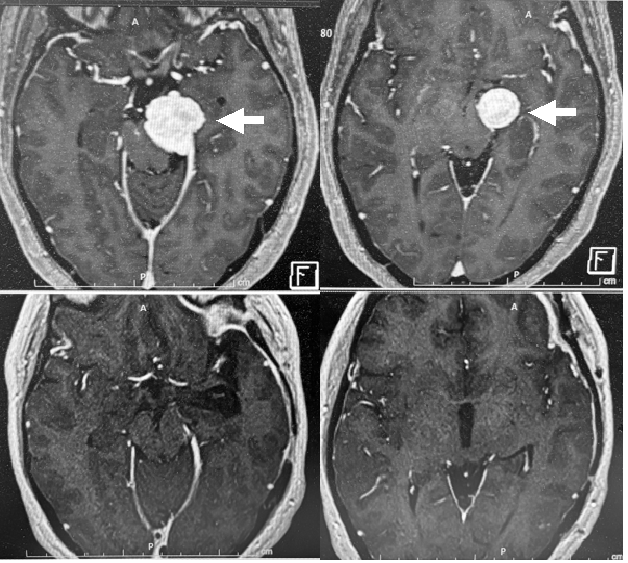

40代女性の左聴神経腫瘍です(左写真白矢印)。腫瘍が大きいために開頭腫瘍摘出を行いました.幸い腫瘍は全摘出することができました.術中,0.03mAの電気刺激に対する良好な反応を維持することができ,術後に顔面神経麻痺は生じませんでした.術前有効聴力がありましたが温存できなかったため,蝸牛神経は切断して腫瘍を摘出しました。術後のMRIでは,腫瘍は写っていません(右写真)。

40代の女性に生じた髄膜腫(一番左の写真の赤矢印)です。腫瘍は脳幹部、小脳のほかに顔面神経や聴覚の神経を強く圧排しています。腫瘍は手術により全摘出できました(左から2番目の写真)。腫瘍による聴覚の神経圧迫が原因で手術前には腫瘍がある側の耳はほぼ聞こえていませんでしたが(右から2番目が手術前の聴力検査の結果です)、手術後には聴力が回復しました(一番右側が手術後の聴力検査の結果です)。